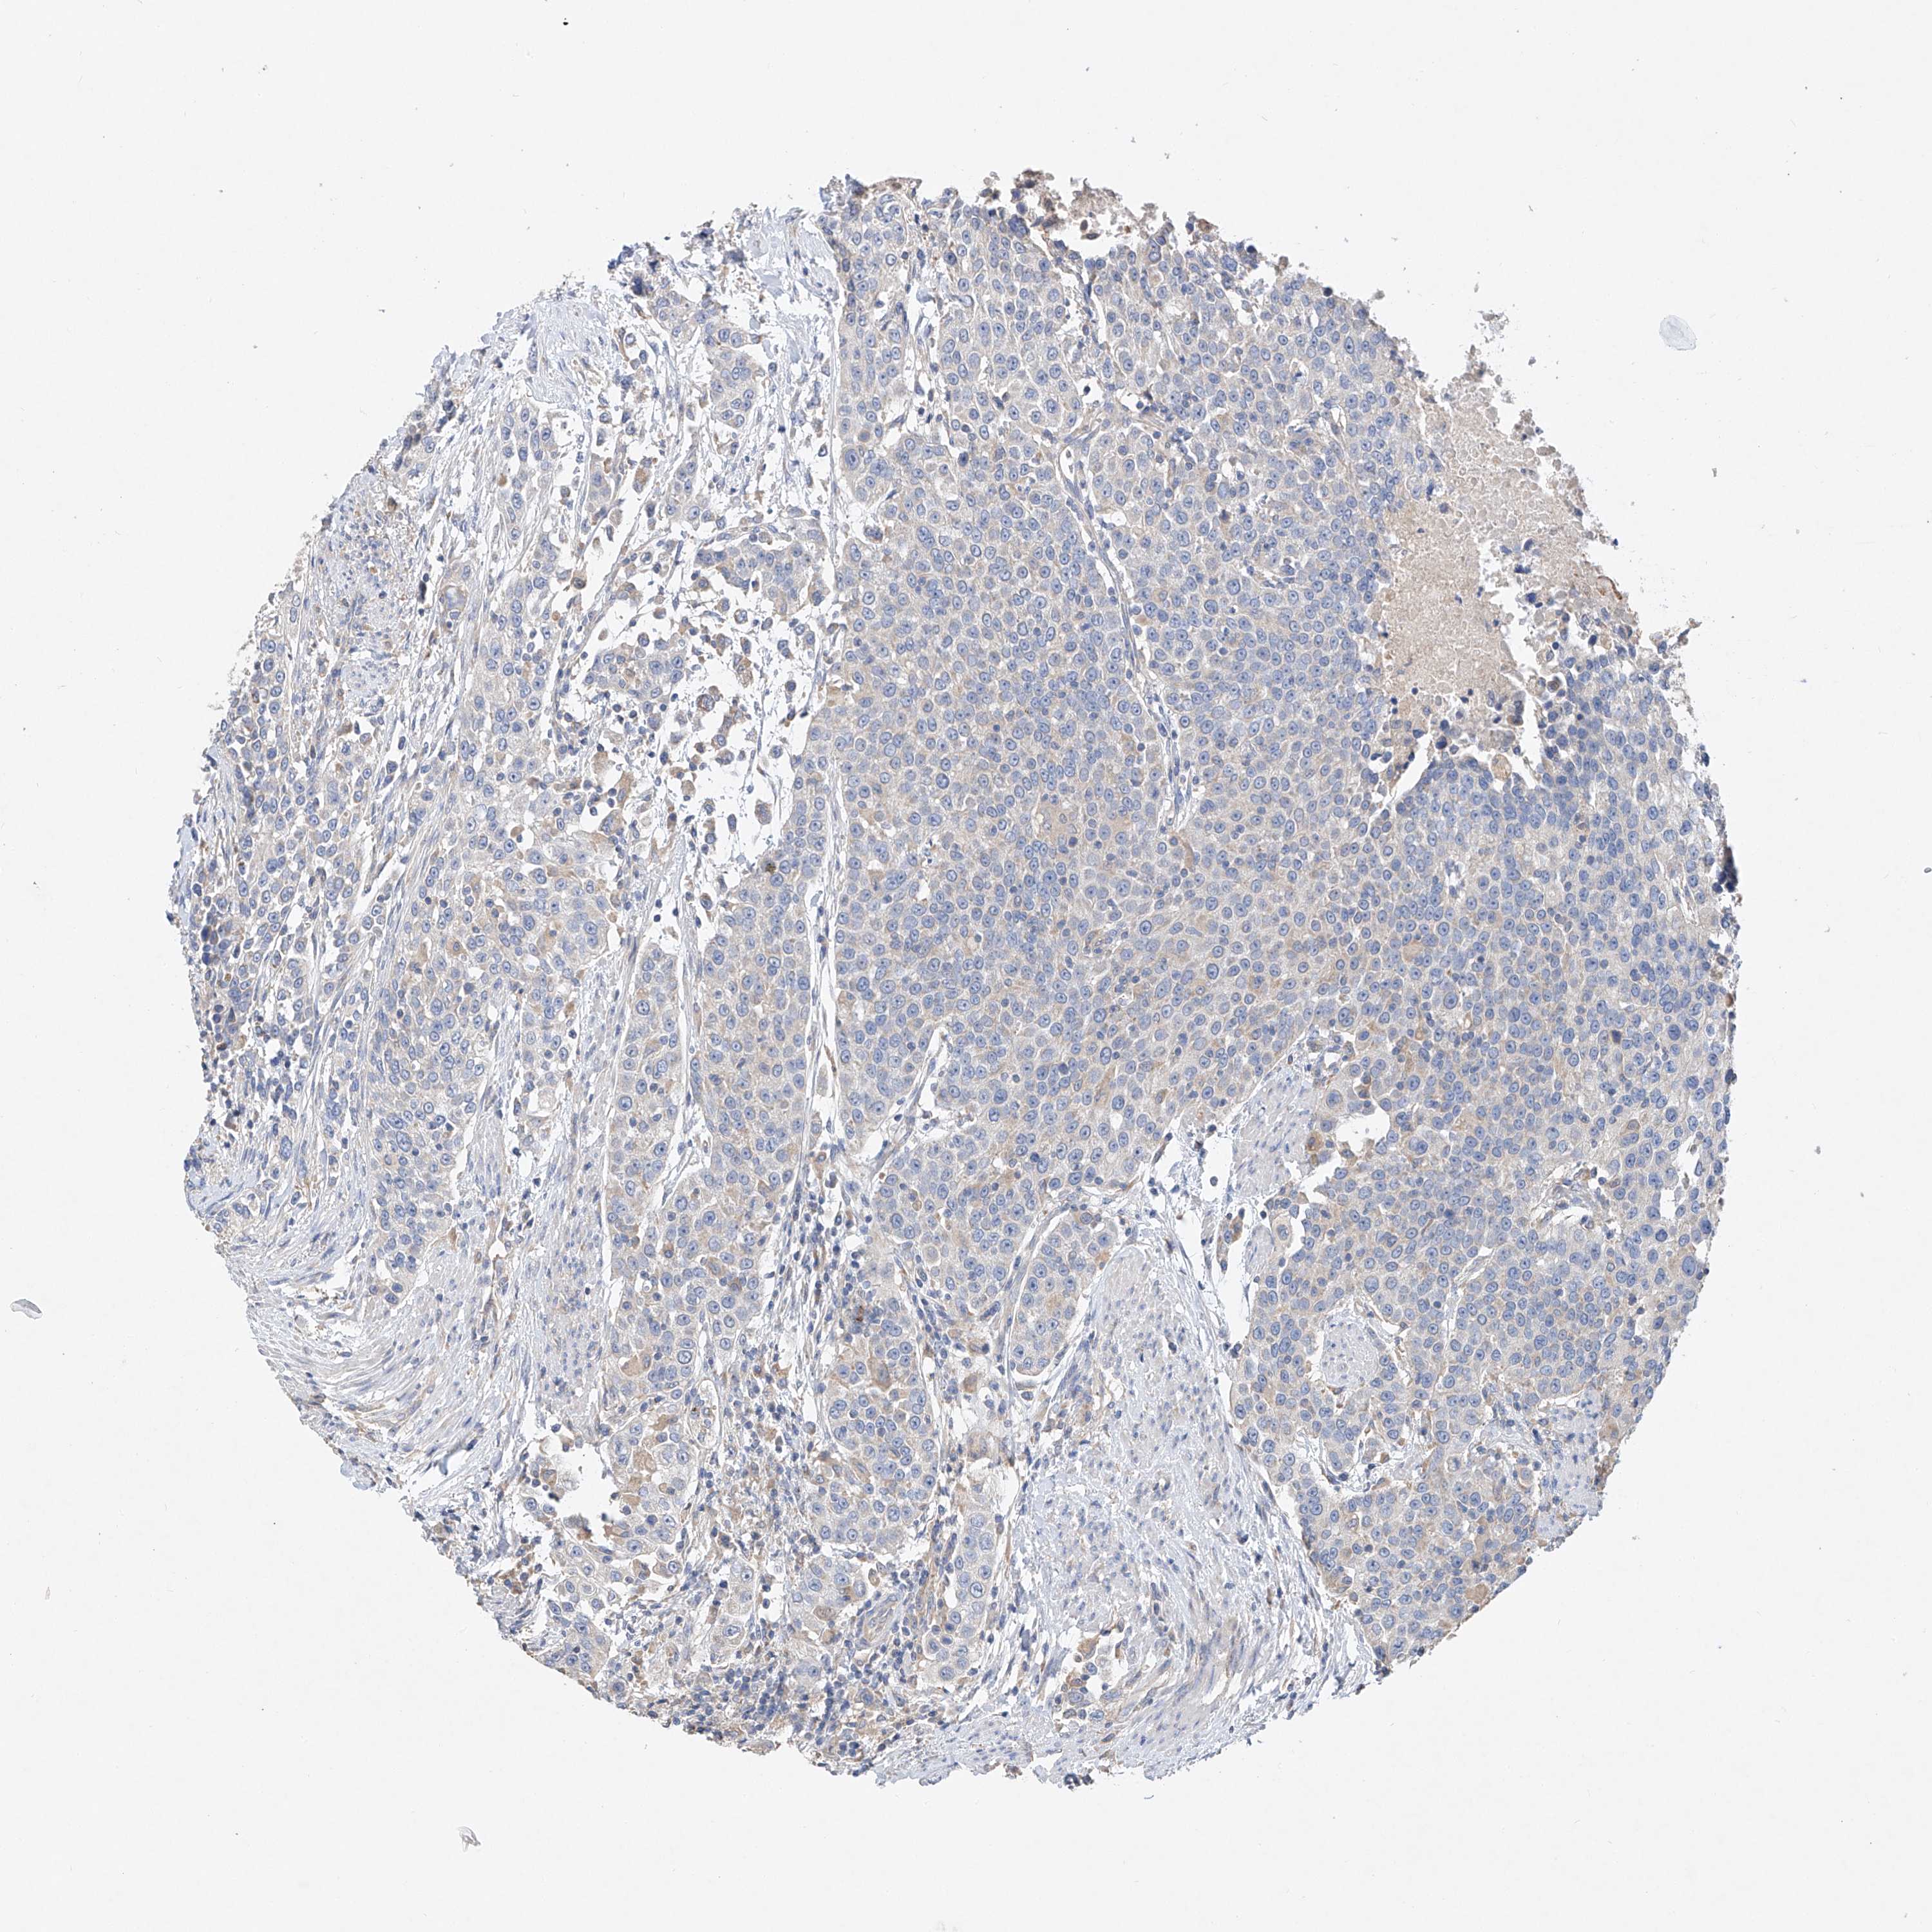

UROTHELIAL CANCER - Protein expressioni

A mouse-over function shows sample information and annotation data. Click on an image to view it in a full screen mode. Samples can be filtered based on level of antibody staining by selecting one or several of the following categories: high, medium, low and not detected. The assay and annotation is described here.

Antibody stainingi

Antibody staining in the annotated cell types in the current human tissue is reported as not detected, low, medium, or high, based on conventional immunohistochemistry profiling in selected tissues. This score is based on the combination of the staining intensity and fraction of stained cells.

Each image is clickable and will lead to virtual microscopy that enables deeper exploration of all samples and also displays staining intensity scores, fraction scores and subcellular localization as well as patient and tissue information for each sample.

Antibody HPA029281

Antibody HPA029282

Staining

High

Medium

Low

Not detected

Intensity

Strong

Moderate

Weak

Negative

Quantity

>75%

75%-25%

<25%

None

Location

Nuclear

Cytoplasmic/membranous

Cytoplasmic/membranous,nuclear

Urothelial carcinoma, Low grade

Urothelial carcinoma, High grade